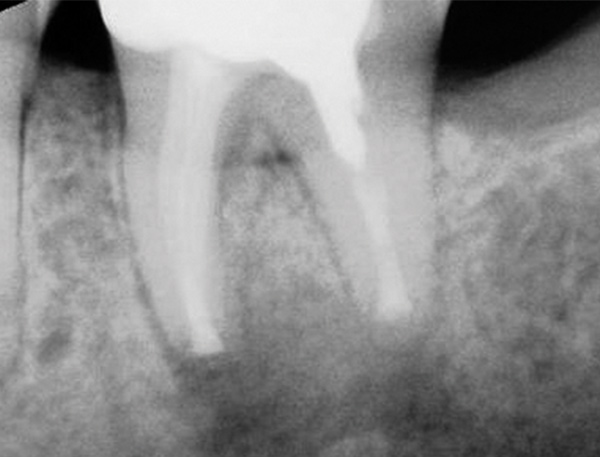

The next step in the diagnostic process was to perform objective clinical sensibility pulpal and periradicular testing to determine the etiology of the patient's chief complaint. A periapical radiograph was taken of tooth No. 18 that showed a radiolucent area present around both the mesial and distal roots(Figure 3). Tooth No. 18 tested abnormal to percussion and bite tests. Palpation, periodontal probings, and mobility were within normal limits. Tooth No. 17 had been previously extracted, and tooth No. 19 tested within normal limits to cold, percussion, palpation, bite test, mobility, and periodontal probing sensibility tests.

Preoperative periapical radiograph of tooth N o. 18.

Fig 3.